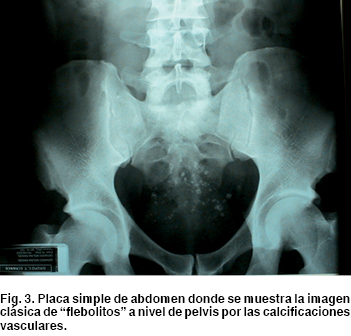

La placa simple de abdomen hace evidente, a nivel del sacro, calcificaciones secundarias a microtrombosis de los vasos del hemangioma causados por inflamación perivascular y estasis del flujo sanguíneo, estas calcificaciones se llaman flebolitos, es un signo patognomónico en esta patología, se pueden encontrar entre un 26-50% (Figura 3). Además, existe desviación de la columna de aire del recto, siendo más notorio en el colon por enema con contraste de bario, donde se demuestra un desplazamiento del recto como efecto de compresión extrínseca (Figura 4). Existe también el aspecto de seudopólipos en la mucosa por la gran dilatación venosa submucosa, en otros casos puede dar la apariencia de una obstrucción circunferencial de la luz.4,7,10,11,15,16,18,22